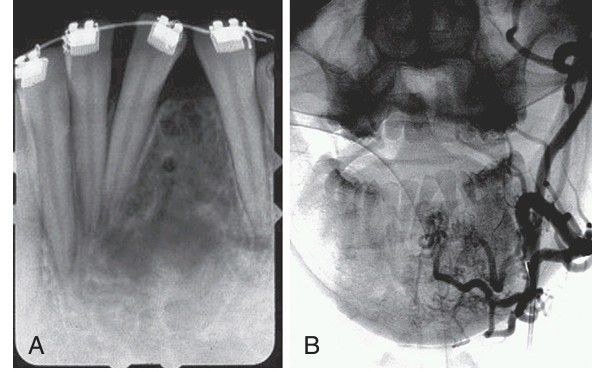

. A, Periapical radiograph showing an expansile, mottled radiolucency in the mandibular incisor region. Pulsatile hemorrhage was encountered when a biopsy of this lesion was attempted. B, Angiogram demonstrating a vascular proliferation between the mandibular incisors.